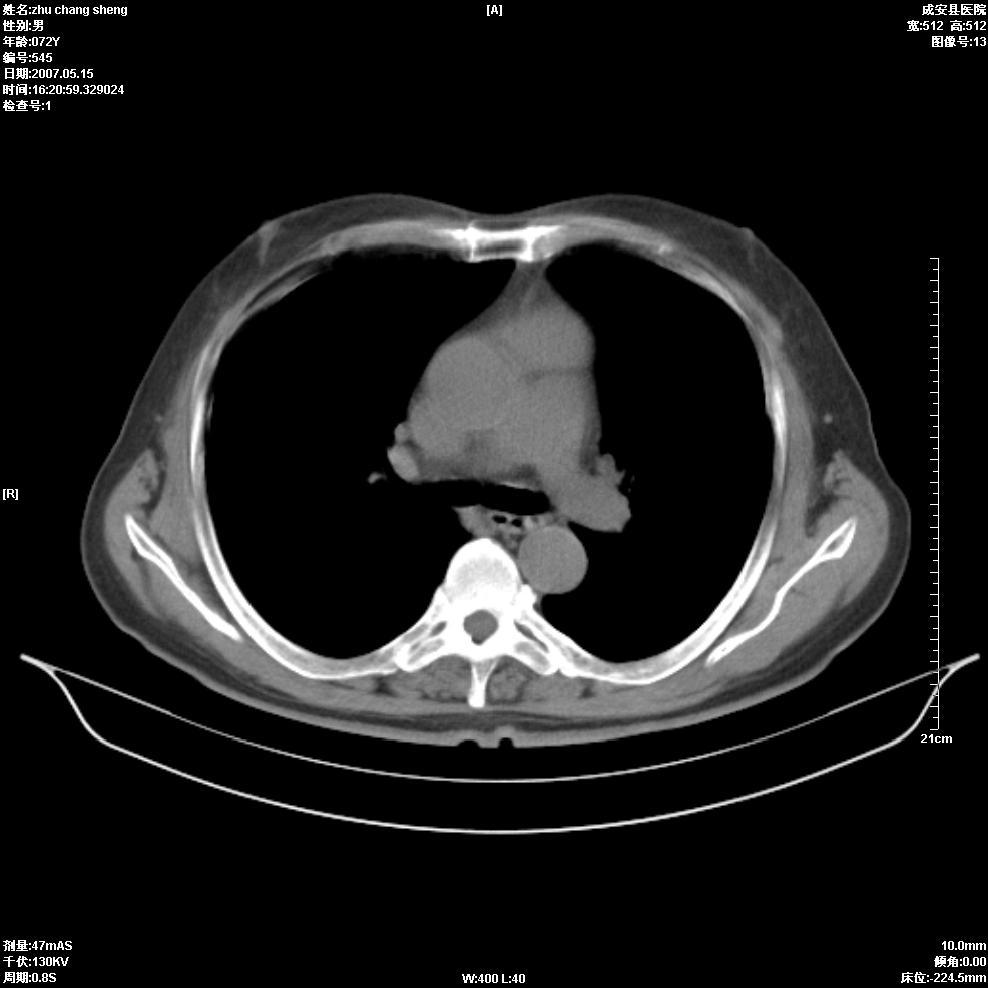

以下是引用医博云天在2007-5-15 19:10:00的发言:[br]心包积液,胸腔积液,心影增大,左心为主。

以下是引用zhangzhongshou在2007-5-15 20:21:00的发言:[br]心包积液可以肯定有,肿块显示不清,建议增强或mri检查。

以下是引用拾荒者在2007-5-15 22:28:00的发言:[br]心包膜增厚,有少量积液,右室前壁示均匀软组织密度影,边界欠清,建议增强扫描或mri检查与室壁瘤鉴别。

以下是引用还珠格格在2007-5-19 9:50:00的发言:[br]病人与5月18日 做了核磁增强扫描 确诊为前上纵隔侵袭性胸腺瘤。